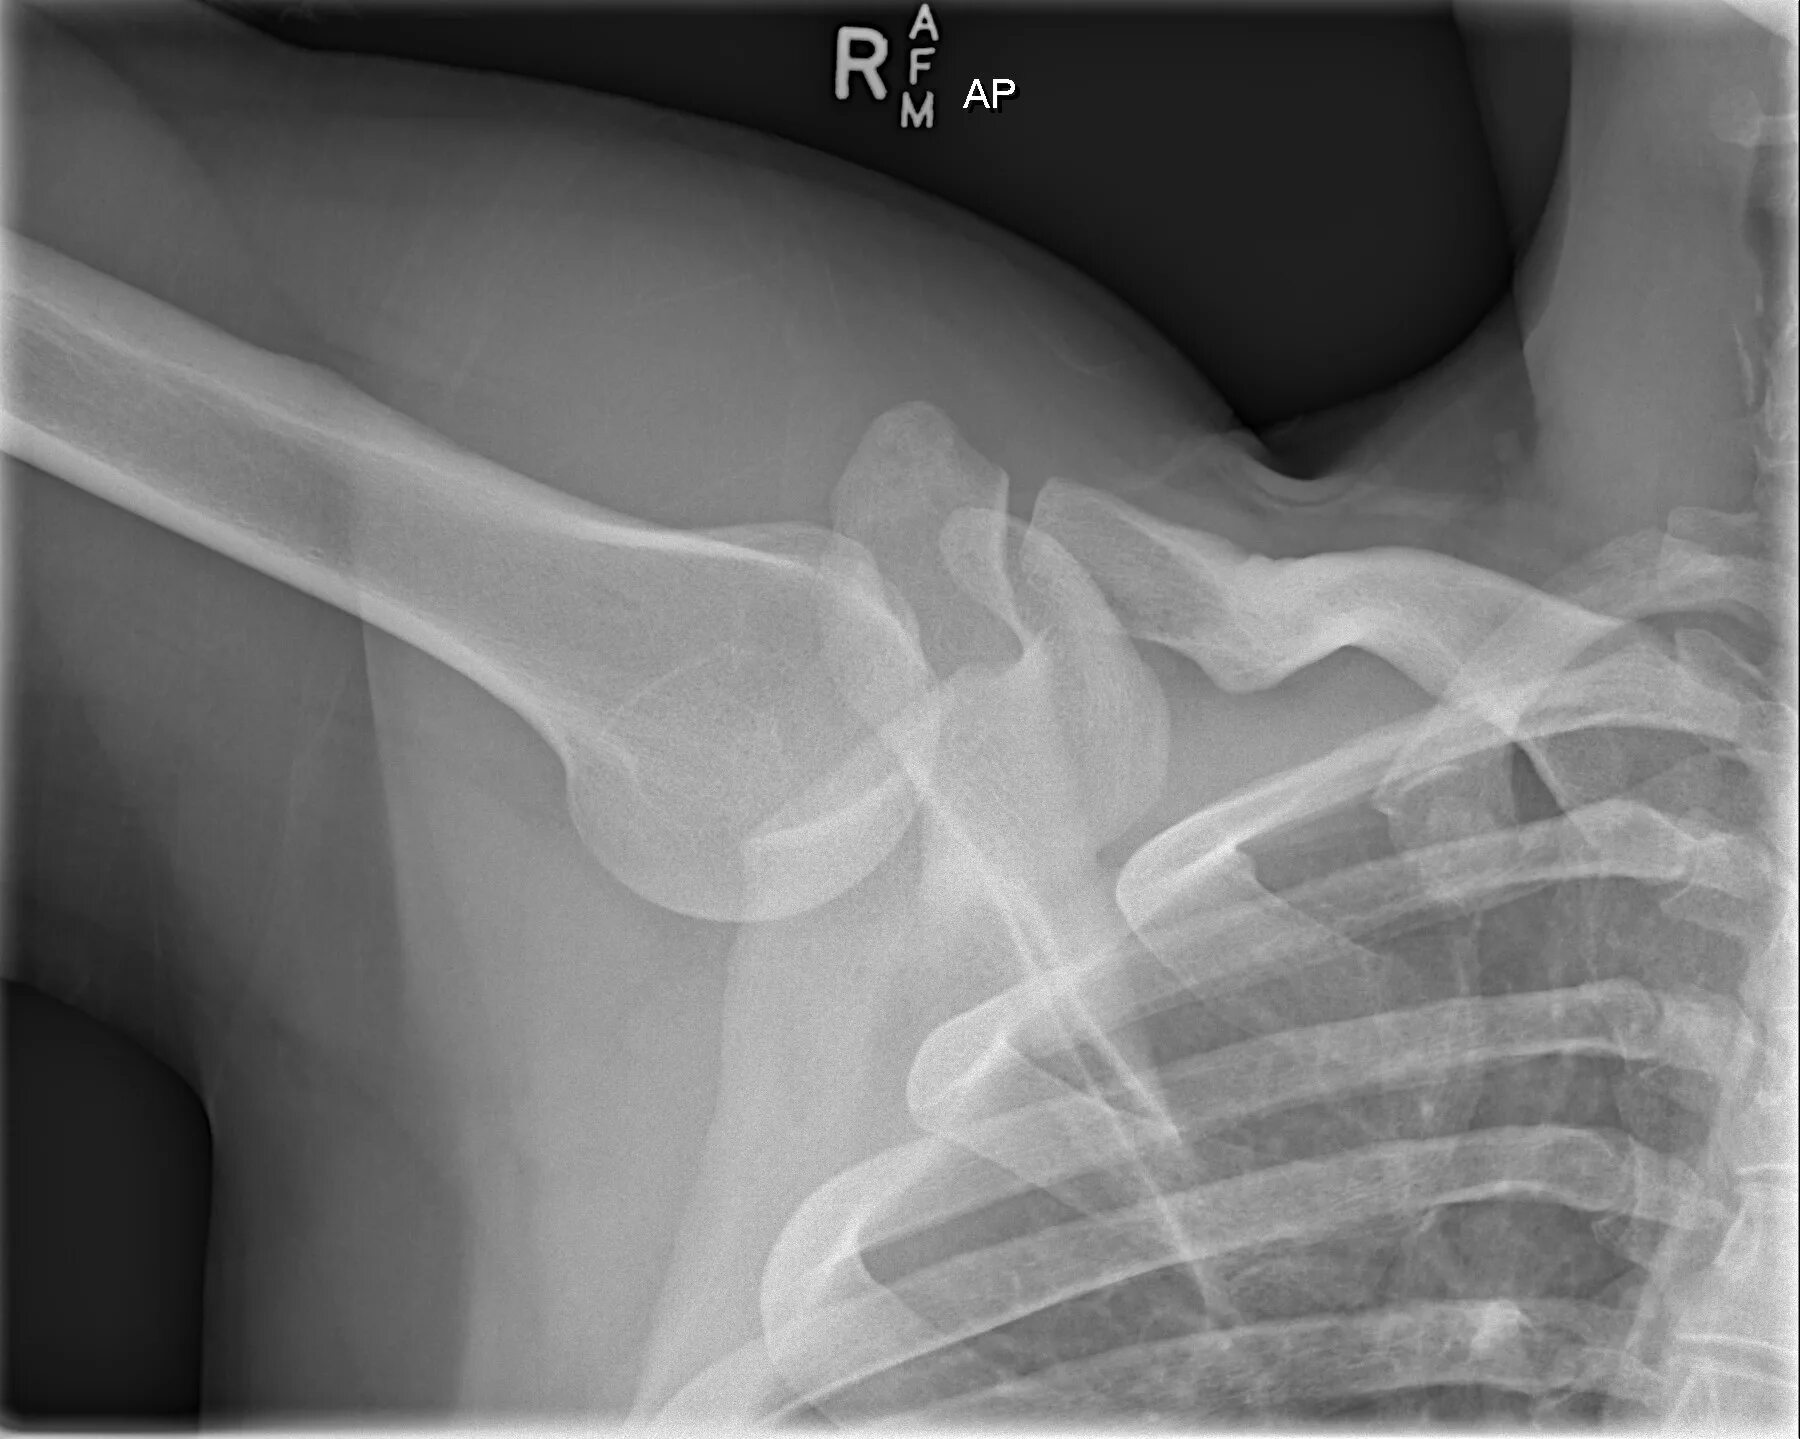

Вывих плеча у пожилых